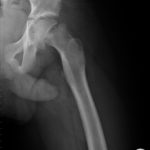

Slipped Capital Femoral Epiphysis(SCFE)

Slipped capital femoral epiphysis refers to the atraumatic separation of the epiphysis in the epiphyseal plate of the femoral neck with displacement of the femoral head, usually in a medial and dorsal direction, during the pubertal growth spurt……